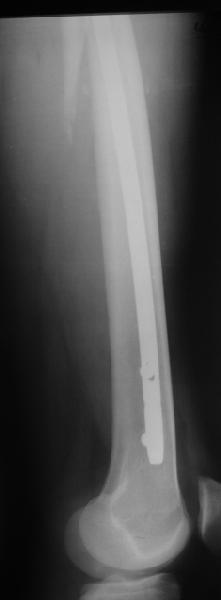

В диагноз пишем... Потом же как-то анализировать надо. Что-то никто не откликнулся на этот вопрос из англоязычных коллег. Все-таки - как такой перелом надо классифицировать? А если шейка бедра + диафиз? Завтра покажу такой случай.

Реконструкционный гвоздь.

Да, сейчас это и у нас самый напрашивающийся выбор. Сделали гвоздем ChM, картинки в приложении.